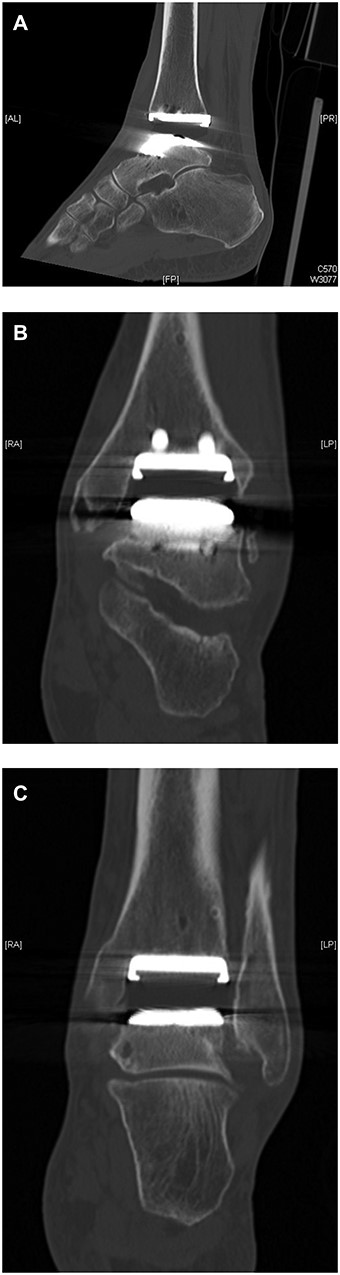

(A, B) Intraoperative pictures of polyethylene liner demonstrating incomplete seating into replacement.

Revision ankle surgery was undertaken by anterior approach through the previous incision. Intraoperative samples were taken which ruled out infection. The tibial component was well fixed to bone and showed no evidence of loosening, subsidence or rotational malalignment. Macroscopic examination of the retrieved insert showed grooves on its side. The poly was not fully reduced in its groove and had dislodged from the groove subsequently on the posterior aspect of the implant (Fig. 2A and B). He had a revision of the talar component to size 2 and change of polythene with good clearance of his medial gutter.